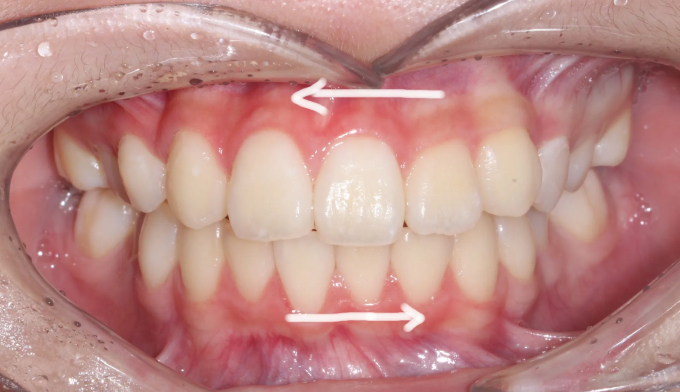

덧니,

돌출입

10대

2025.02.11